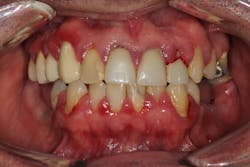

Medication-induced (drug-induced) gingival enlargement can be caused by certain classes of drugs people may be taking.1 The following classes of drugs have been associated with gum overgrowth:

- 50% of the cases are typically attributed to phenytoin (figure 3).

- 10% to 20% of the cases are typically attributed to calcium channel blockers, with nifedipine being the most notable problem (figures 4a and 4b).